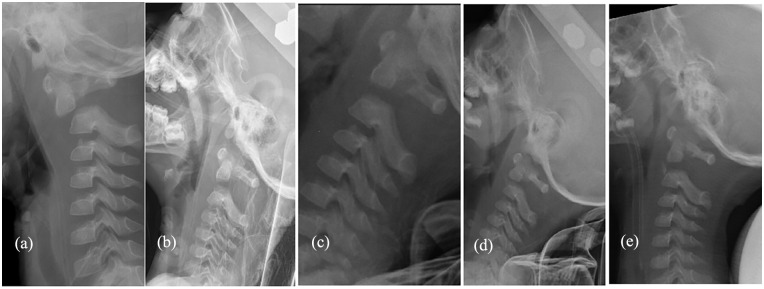

Results: We treated three patients (boy:girl = 0:3, mean age = 2.5 years old) from 2017 to 2020, the diagnoses were all traumatic C1-2 infra-anterior dislocations associated with odontoid fracture (Anderson and D'Alonzo classification type II: three cases, Hosalkar type IB: two case and IC: one case), with or without cervical spinal cord injury. The C1-2 infra-anterior dislocations were all successfully reduced by gentle traction with the halo method (case 1) or occipital-jaw (cases 2 and 3) for a mean of 18.3 days (19, 15, 21 days), after which the Calot plaster vests (head-neck-chest plaster vests) were fitted and maintained for 2 months, without operation. Braces were maintained for 3 months after the Calot plaster vests were removed. All patients achieved fracture healing and recovered from the spinal injury.

Conclusion: In young children, atlantoaxial joint infra-anterior dislocation complicating odontoid fracture usually occurred at the odontoid synchondrosis and belonged to Anderson and D'Alonzo classification type II or Hosalkar type I. Conservative treatment achieved good results (dislocation reduction, bone healing, recovery of neurological symptoms).